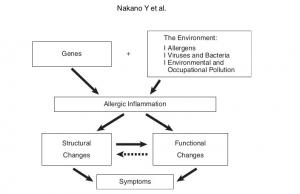

Radiological Approach to Asthma and COPD-The Role of Computed Tomography.